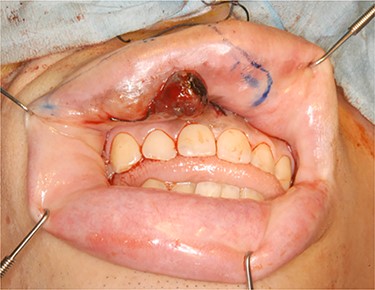

A 20-year-old male patient was referred to our hospital with a small black-colored polyp on the upper lip. On clinical examination, a small polyp measuring 10 × 8 mm in size at the right side of the upper lip mucosa with a brown–black patch expanding from gingivolabial sulcus to the attached gum of incisor tooth was observed (Fig. 1). He was clinically diagnosed with a mucosal malignant melanoma with a metastatic right submaxillary lymph node (Fig. 2). The brown–black patch was melanoma in situ. The polyp was found to be a malignant melanoma following a biopsy. Tumor resection with radical neck dissection was performed 5 days after the biopsy. The tumor excision site was planned, involving some orbicularis oris muscle, including oral mucosa, gingiva and alveolar bone extending from the right canine tooth to the left central incisor tooth (Fig. 3). The defect in the red lip was reconstructed using a musculomucosal flap from the lower lip; simultaneously, the perioral defect was reconstructed using a tongue flap. Initially, the intraoral defect was filled using a tongue flap to the greatest extent possible (Fig. 4). A 10-mm width musculomucosal flap including the right inferior labial artery, in which blood flow had been detected using Doppler ultrasound after right side neck dissection, was designed at the lip mucosa, reaching the left side beyond the center of the lip (Fig. 5). Both the right vermillion border and the shortage of intraoral reconstruction by the tongue flap were repaired using a lip musculomucosal flap (Fig. 6). Both flaps healed well without any congestion or necrosis. They were separated at 2 weeks after primary surgery under deep sedation. The patient could eat and speak without trouble. Nevertheless, cupid’s bow was conspicuous for the gap and the postoperative scar contracted after 3 months. Therefore, correction of the cupid’s bow using Z-plasty of the white lip and reduction of the tongue flap was performed. The secondary operation to correct the misalignment of cupid’s bow and to remove the contraction was successful (Fig. 7).

Operative finding. The tumor was excised with some orbicularis oris muscle including the oral mucosa, gingiva and alveolar bone from the right canine tooth to the left incisor.